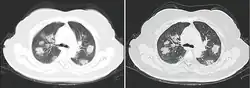

A CT scan of a person with COVID-19 shows lesions (bright regions) in the lungs

CT scan of rapid progression stage of COVID-19

Chest CT scans may be helpful to diagnose COVID‑19 in individuals with a high clinical suspicion of infection but are not recommended for routine screening.[175][187] Bilateral multilobar ground-glass opacities with a peripheral, asymmetric, and posterior distribution are common in early infection.[175][188] Subpleural dominance, crazy paving (lobular septal thickening with variable alveolar filling), and consolidation may appear as the disease progresses.[175][189] Characteristic imaging features on chest radiographs and computed tomography (CT) of people who are symptomatic include asymmetric peripheral ground-glass opacities without pleural effusions.[190]

Many groups have created COVID‑19 datasets that include imagery such as the Italian Radiological Society which has compiled an international online database of imaging findings for confirmed cases.[191] Due to overlap with other infections such as adenovirus, imaging without confirmation by rRT-PCR is of limited specificity in identifying COVID‑19.[190] A large study in China compared chest CT results to PCR and demonstrated that though imaging is less specific for the infection, it is faster and more sensitive.[174]